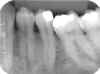

ANOMALIAS

1